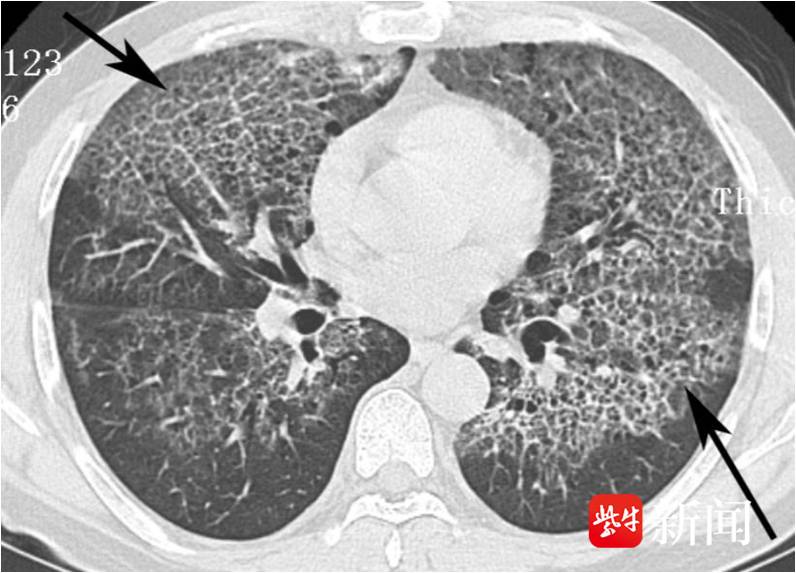

胸部CT检查结果出来后,医生发现了端倪:他的肺部布满了散在的磨玻璃影,小叶间隔明显增厚,呈现出典型的 “铺路石征”。

检查影像

“这种‘铺路石’样的影像,常见于多种疾病,既可能是病毒或细菌感染,也可能是间质性肺病,甚至是肿瘤相关病变。” 呼吸与危重症医学科主任钱粉红解释道。

影像特征:除了老凌身上出现的 “铺路石征”,还可能有 “地图征”—— 病变与正常肺组织分界清晰,就像地图上的不同区域。